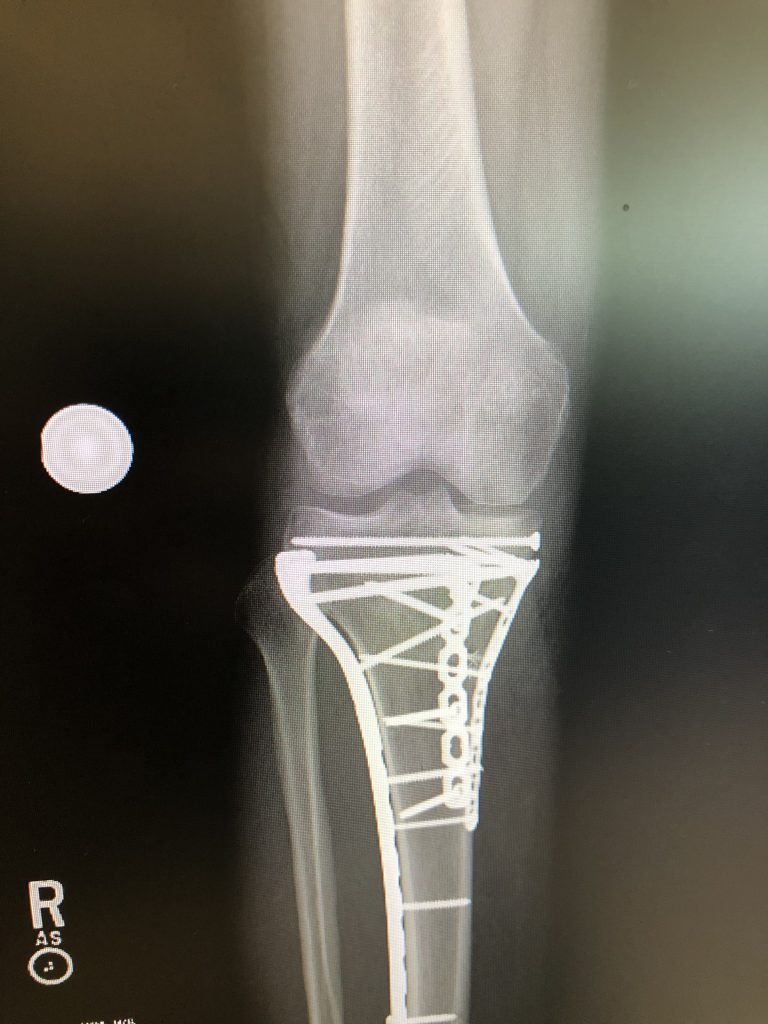

The surgery was extremely complex and took nearly 9 hours start to finish but Dr. Dvorzhinskiy, with the help of resident Dr. Gregory Kazarian, successfully rebuilt my shattered leg. My post-operative x-rays are a testament to his incredible talent as a surgeon and the way in which he reconstructed the shattered tibia and salvaged the detached cartilage enabled me to recover to the point where less than 9 months after the surgery I can walk and even exercise with minimal pain and have a long active and healthy life to look forward to.